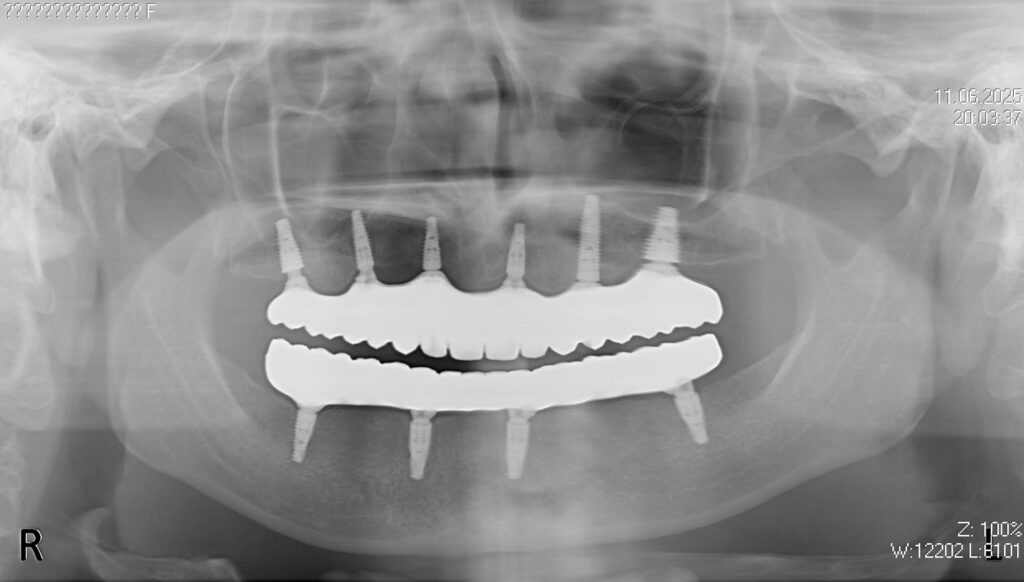

Пациент обратился к нам с целью перепротезирования на постоянные протезы (комплексная имплантация по системе All-on-6 на обе челюсти была проведена в 2024г. специалистами нашей клиники).

По прошествию года было изготовлено 2 постоянных циркониевых протеза на титановой балке.

6-ти дентальных имплантантах Megagen Anyone